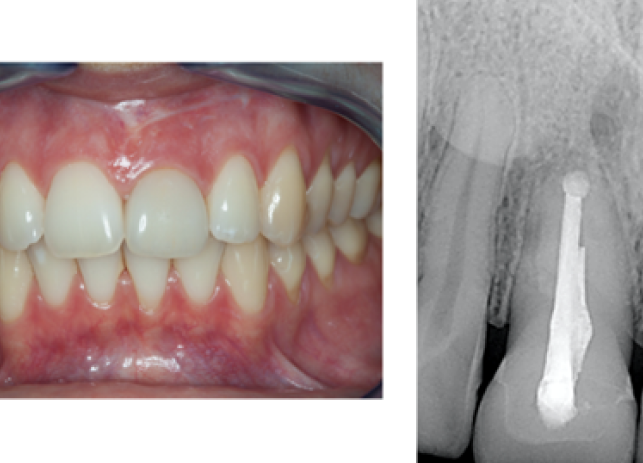

Рис. 9 и 10 после начального заживления временная коронка была адаптирована с помощью композита для тренировки и формирования мягких тканей, аналогично прилегающему правому центральному резцу. Нашей целью также было добиться одинаковой длины 11 и 21 зубов или выровнять высоту десны